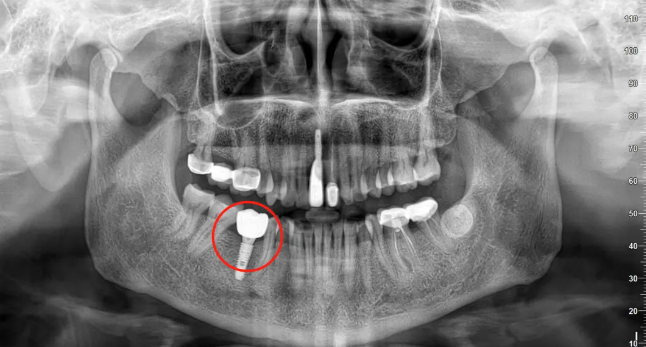

🔎种植牙

△种植牙等修复体在全景片上通常呈现白色。